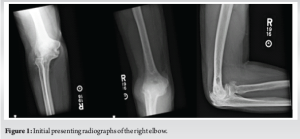

A 50-year-old right-hand dominant male presented to the orthopedic office for evaluation of chronic right elbow pain. He states this has been ongoing since he sustained an injury, while in the military, about 7 years ago. Over this period, he underwent 7 different surgeries related to this injury, with the most recent procedure in January of 2011. He noted considerable pain, stiffness, and significant difficulty performing tasks at work and activities of daily living. His pre-operative Visual Analog Scale (VAS) pain score was a 10 out of 10, mayo elbow performance score (MEPS) was 15/100 (<60 indicating poor performance), American shoulder and elbow surgeons (ASES) score of 18/100, and disabilities of the arm, shoulder and hand (DASH) score of 70/100 with additional noted severe difficulty performing his required work activities as a sports photographer. He also indicated that he was unable to participate in bowling, his sport of most importance, on pre-operative questionnaires. Radiographs and a computed tomography scan were obtained, which demonstrated advanced degenerative changes in the radiocapitellar and ulnohumeral joints (Fig. 1). Given his age, job requirements, and lifestyle, we felt the patient would not be a great candidate for a total elbow replacement given the activity and post-operative weight restrictions. Instead, we recommended treatment with an interpositional arthroplasty for the treatment of his post-traumatic osteoarthritis (Figs. 2 and 3).